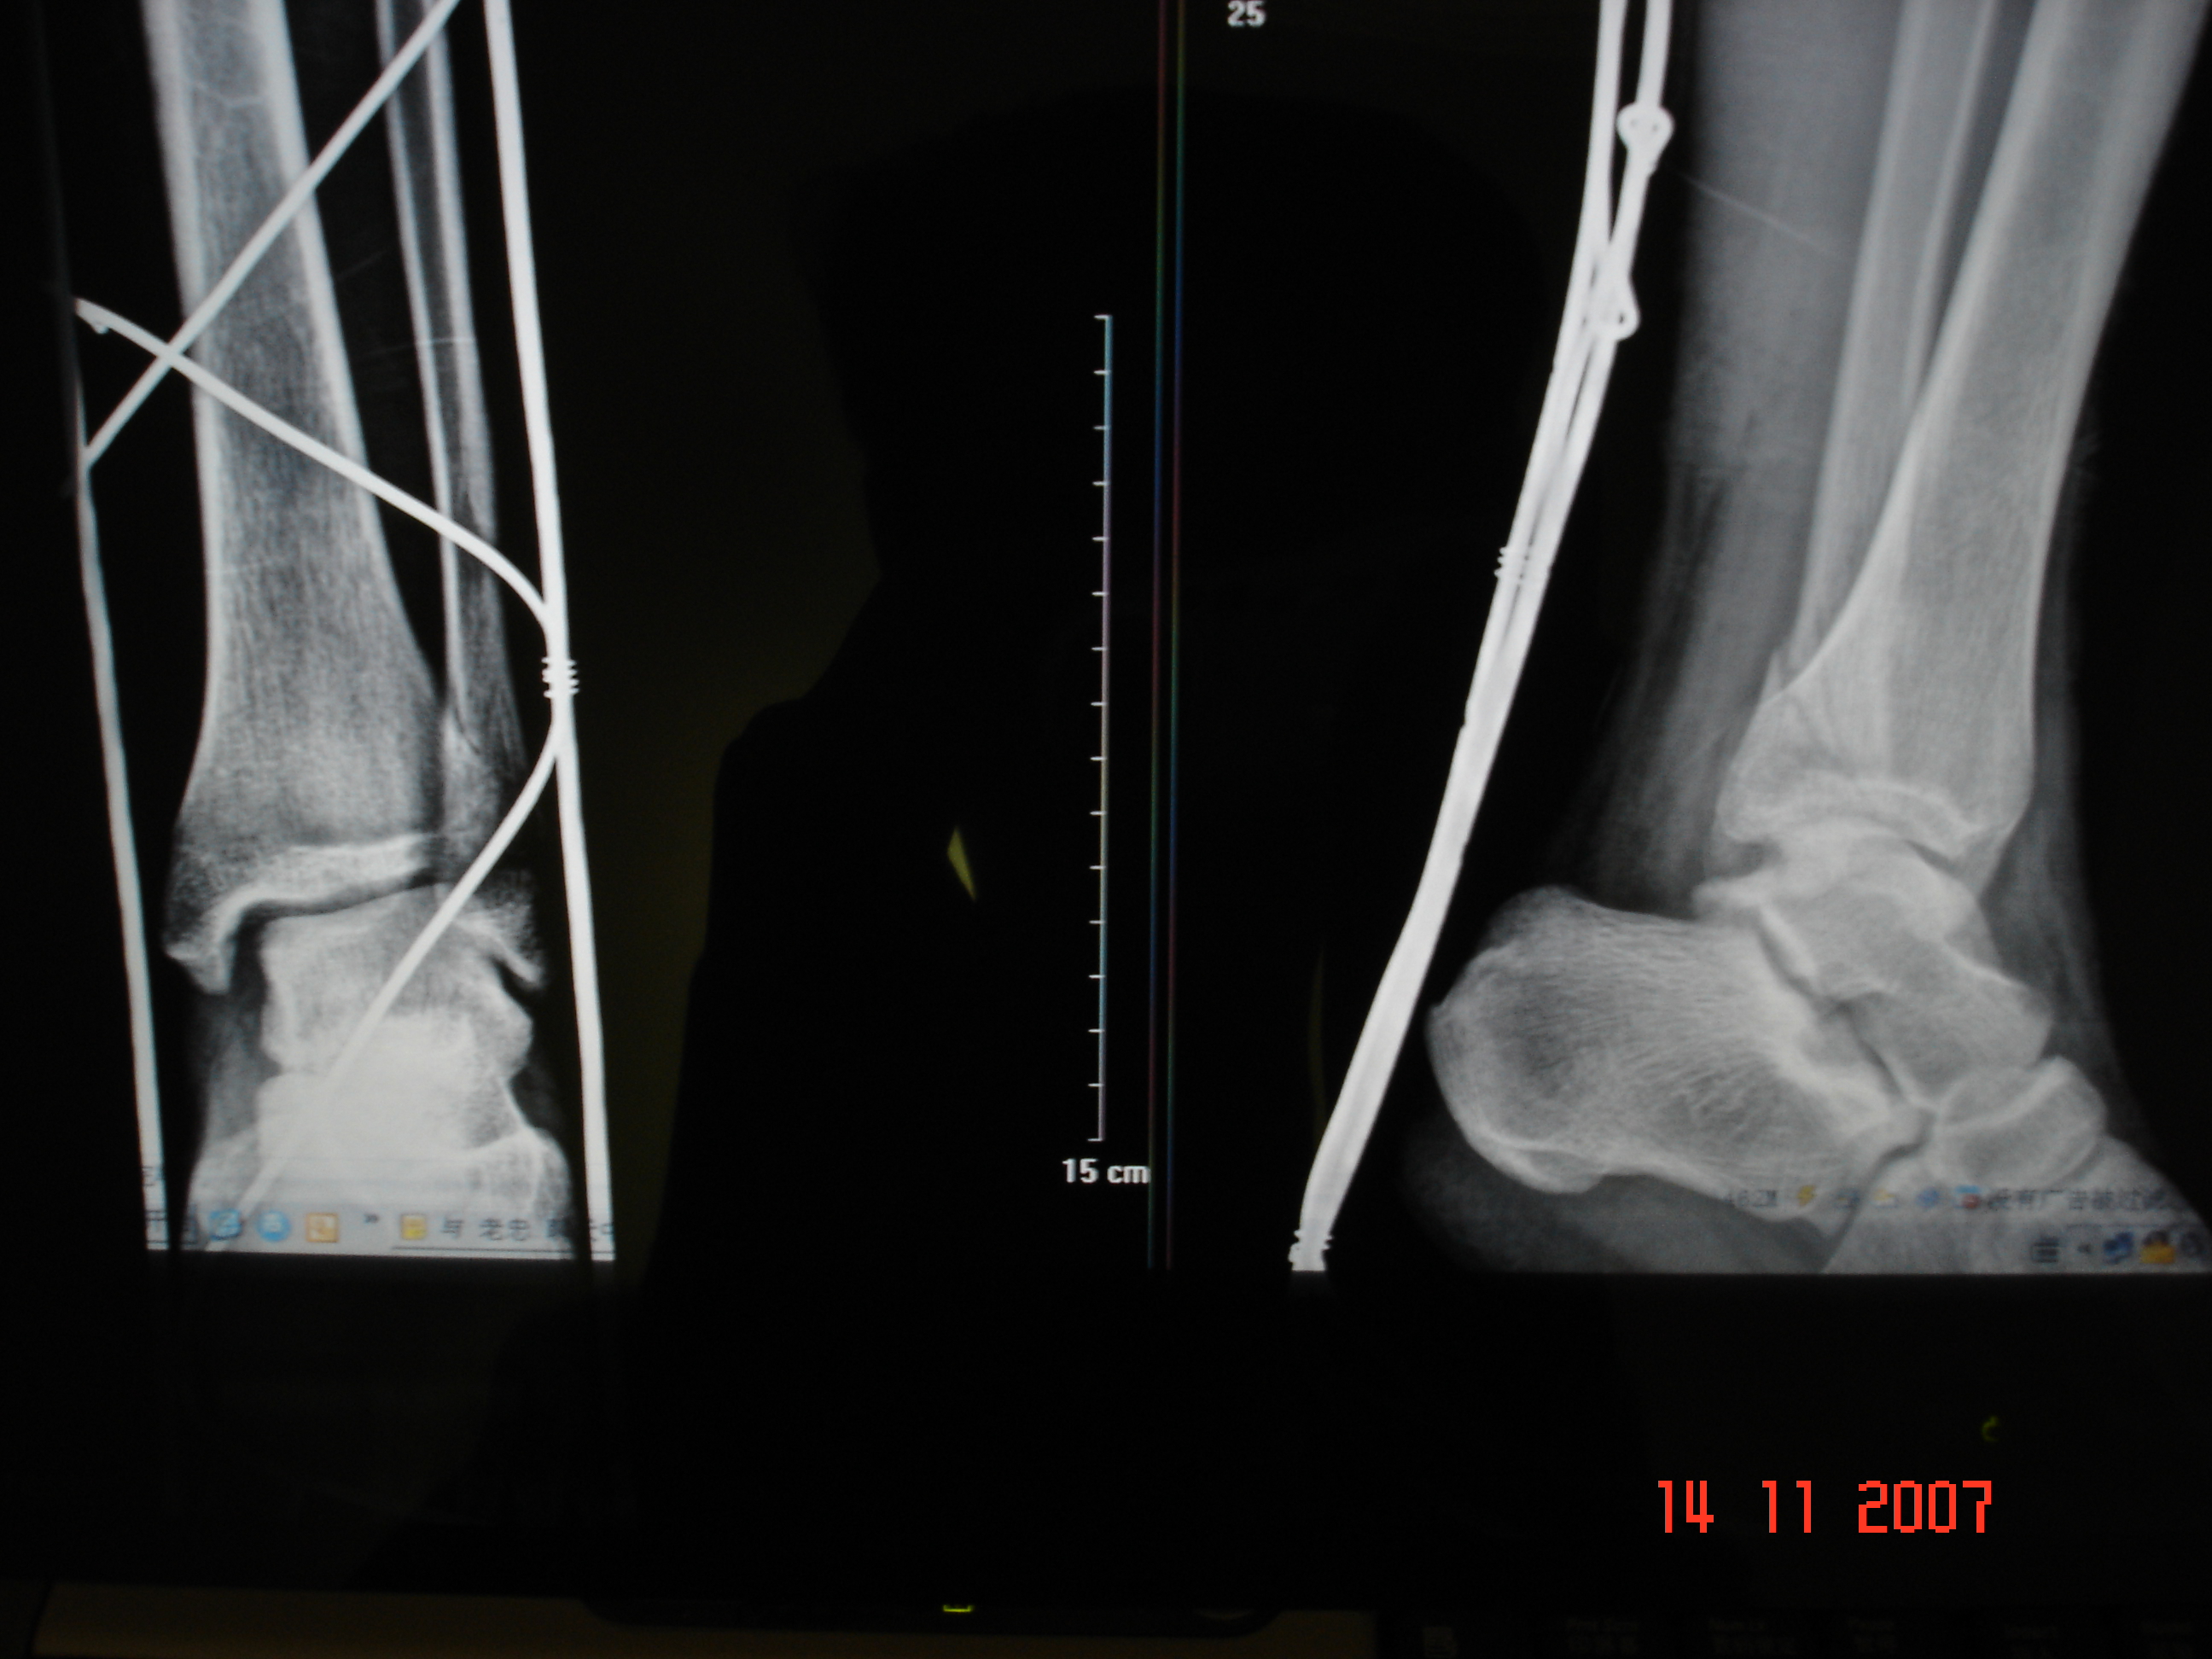

·骨科大夫咨询

·肱骨小头骨折,专家帮帮我...